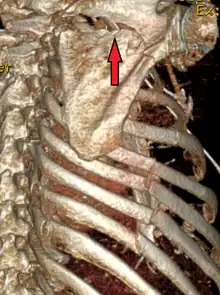

| A right sided scapula fracture with rib fractures underneath seen on a 3D reconstruction of a CT scan | |

Most fractures of the scapula can be seen on a chest X-ray; however, they may be missed during examination of the film.[1] Serious associated injuries may distract from the scapular injury,[4] and diagnosis is often delayed.[3] Computed tomography may also be used.[1] Scapular fractures can be detected in the standard chest and shoulder radiographs that are given to patients who have had significant physical trauma, but much of the scapula is hidden by the ribs on standard chest X-rays.[4] Therefore, if scapular injury is suspected, more specific images of the scapular area can be taken.[4]